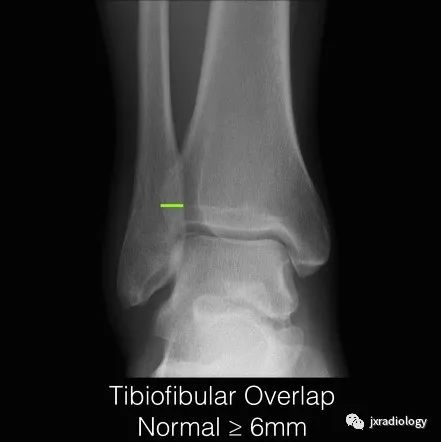

2、正常的踝关节下胫腓联合测量数据:在标准前后位X线片上胫骨远端关节面上1cm水平,下胫腓联合间隙(TFCS)>5mm或胫腓重叠(TFO)在前后位X线片上<10mm,表明存在下胫腓联合损伤。应该进行CT或MRI检查以明确诊断。

下胫腓联合间隙(tibiofibular clear space,TFCS)胫腓骨重叠(tibiofibular overlap,TFO),正常大于6mm